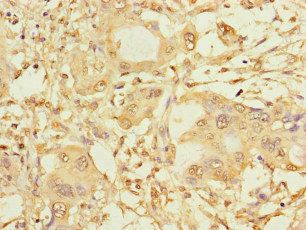

Immunohistochemistry of paraffin-embedded human pancreatic cancer using CSB-PA022470LA01HU at dilution of 1:100

Immunohistochemistry of paraffin-embedded human melanoma using CSB-PA022470LA01HU at dilution of 1:100